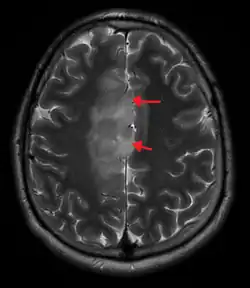

An X-ray computed tomography (CT) or magnetic resonance imaging (MRI) scan is necessary to characterize the anatomy of this tumor as to size, location, and its homogeneity and heterogeneity. However, final diagnosis of this tumor, like most tumors, relies on histopathologic examination (biopsy examination).[4]